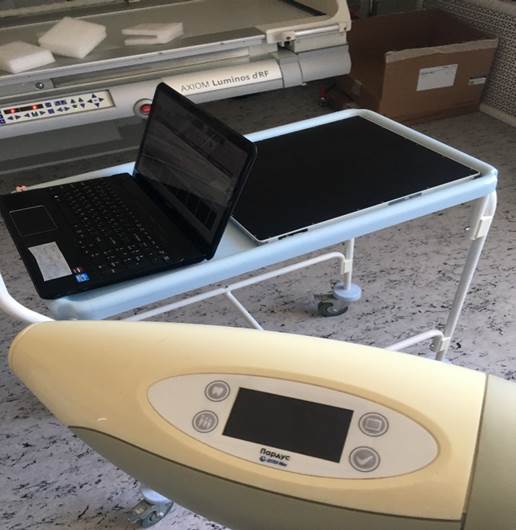

Инновационный цифровой рентгенодиагностический комплекс для неонатологии и педиатрии. Руководитель: Труфанов Г.Е.

Результаты: Разработаны технические средства рентгенодиагностики, в том числе, рентгеновские аппараты, цифровые системы визуализации и штативные устройства (далее рентгенодиагностические комплексы – РДК) в портативном исполнении для неонатологии и портативно-передвижном исполнении для педиатрии. Разработана методика малодозовой микрофокусной рентгенодиагностики, в том числе, определены рентгенооптические и геометрические условия съемки, различные режимы съемки, предложены специальные укладки при рентгенографии новорожденных и детей в возрасте до трех лет (неонатологии и педиатрии).

2. Совместно с учеными из ЛЭТИ усовершенствован современный рентгенодиагностический комплекс для исследования новорожденных. Он включает в себя цифровой рентгеновский аппарат и комплект приспособлений для неонатальной съемки. Комплекс предназначен для эксплуатации как в условиях рентгеновского кабинета, так и в нестационарных неспециализированных условиях.

Рентгенодиагностический комплекс «Пардус» для обследования новорожденных и детей.